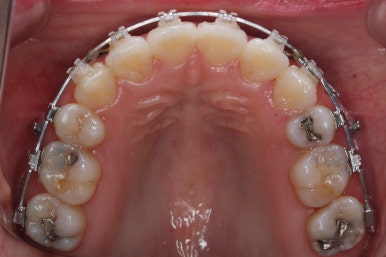

입안 모습입니다.

윗니와 아랫니 모두 각각 보면 가지런해 보이며 발치를 했던 자리도 거의 다 메워져서 양호해 보입니다. 훑어 보면 굳이 더 교정을 해야할 부분이 있을까? 싶겠지만 다음 사진을 보면 알 수 있습니다.